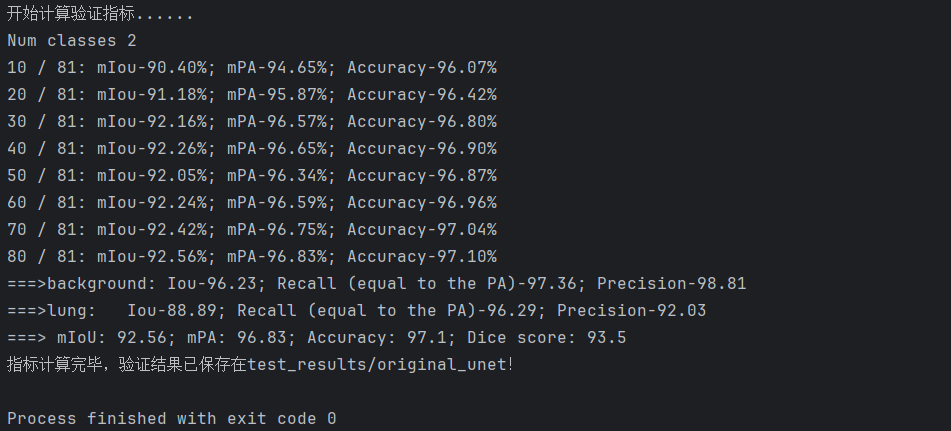

以我们的数据为例,下面是改进模型1得到的结果。